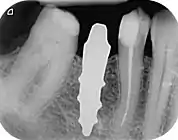

A root analogue implant can be fabricated from zirconium dioxide (zirconia) or titanium. Successful titanium RAIs have been three-dimensionally printed as porous one-piece implants, using CAD software.[4] However, zirconia is the preferred material, because it is more esthetic in color, with no grey discoloration visible through gums.[5][1]

A new attempt was made by Pirker et al 2004 in a human trial with root analogue zirconia implants, but this time by applying differentiated osseoingration on the surface. In 2011 he reported 90% success rate with this method in a 2.5 year human trial.[11]

Mangano et al in Italy in 2012 reported the successful clinical use of a custom-made root analogue implant made by direct laser metal forming (DLMF) from a CBCT scan. This demonstrated that it is possible to combine CBCT 3D data and CAD/CAM technology to manufacture root-analogue implants with sufficient precision.[24]

- ↑ Pirker, W; Kocher, A (2008). "Immediate, non-submerged, root-analogue zirconia implant in single tooth replacement". International Journal of Oral and Maxillofacial Surgery. 37 (3): 293–5. doi:10.1016/j.ijom.2007.11.008. PMID 18272340.

- ↑ Pirker, W; Kocher, A (2009). "Immediate, non-submerged, root-analogue zirconia implants placed into single-rooted extraction sockets: 2-year follow-up of a clinical study". International Journal of Oral and Maxillofacial Surgery. 38 (11): 1127–32. doi:10.1016/j.ijom.2009.07.008. PMID 19665354.

- 1 2 3 Pirker, W; Wiedemann, D; Lidauer, A; Kocher, A (2011). "Immediate, single stage, truly anatomic zirconia implant in lower molar replacement: a case report with 2.5 years follow-up". International Journal of Oral and Maxillofacial Surgery. 40 (2): 212–6. doi:10.1016/j.ijom.2010.08.003. PMID 20833511.